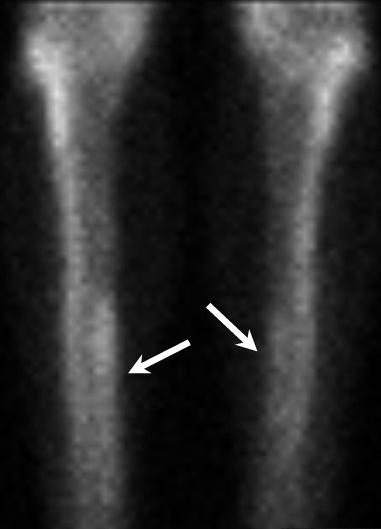

It's important to note that imaging is not useful for diagnosing shin splints. Multiple studies have shown that x-ray, ultrasound, CT scan or bone scans are not sufficient to diagnose MTSS. However, imaging can help rule out the possibility of other conditions, such as a stress fracture.

Bone overloading is a recent proposed mechanism for the development of shin splints. At the tibial border, there is evidence to show decreased bone mineral density in symptomatic individuals. Once bone mineral density improves, symptoms also improve. In some cases, the bone at the injured area showed signs of impaired repair. With the high impact forces and repetitive nature of running, it is logical that these forces can over-stress bone and lead to pain.